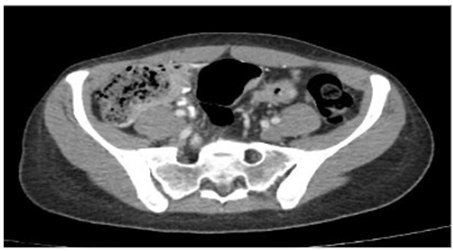

Se decidió realizar una tomografía de abdomen (figura 3) que mostró engrosamiento concéntrico de las paredes del colon sigmoide de 7 mm de espesor, de aspecto inespecífico, de probable etiología inflamatoria, asociado a coprostasis en el colon ascendente y transverso, sin observarse adenomegalias, y endoscopia de vías digestivas altas, cuyo único hallazgo fue gastritis crónica. En la radiografía de tórax de control (figura 4) se aprecian cambios dados por opacidades reticulares bilaterales en 4 cuadrantes y aumento del proceso reticular previo, por lo que se hace necesario la toma de biopsia pulmonar por parte de cirugía de tórax.

Figura 3. Tomografía de abdomen con imagen de engrosamiento concéntrico de las paredes del colon sigmoide.